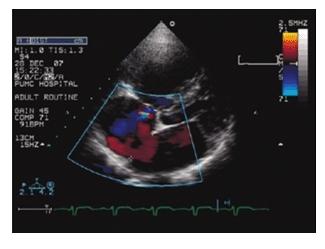

心脏彩超经过前期独立核算试运行三年,科室正式成立于2024年初,已拥有比较完善的心脏、血管超声检查体系。科室技术力量雄厚,现有高级职称2人,中级职称6人,执业医师3人。

现有德国飞利浦高端彩超仪器两台

科室对于临床常见冠心病、急性心肌梗死、高血压性心脏病、肺源性心脏病、心肌炎及心肌病、先天性心脏病、心脏瓣膜病变、颈动脉病变、椎动脉病变、外周动脉栓塞、动脉炎、动脉硬化闭塞症、四肢静脉血栓等均有丰富的超声诊断经验。为需要心脏、血管手术患者提供较为准确的术前评估,为心脏瓣膜置换、先天性心脏病修复、封堵、心脏其它介入手术、颈动脉支架、颈动脉内膜剥脱术后、外周血管支架等提供术后随访检测。